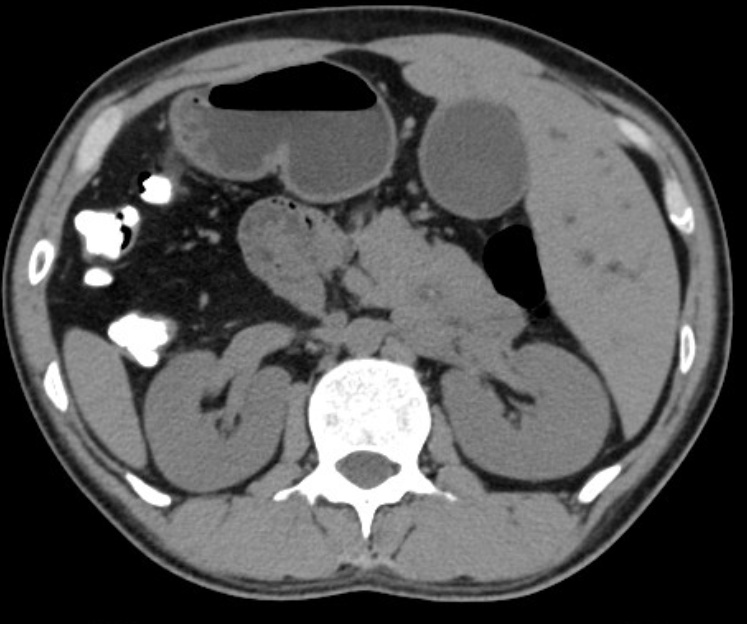

反转的脏器CT影像

患者陈先生因腹痛、肤黄就诊当地医院,经检查确诊为胆总管结石伴胆管炎。然而影像检查提示:右位心,完全内脏反位。面对这百万分之一的变异,当地的医生束手无策。陈先生慕名来到孟超肝胆医院就诊。